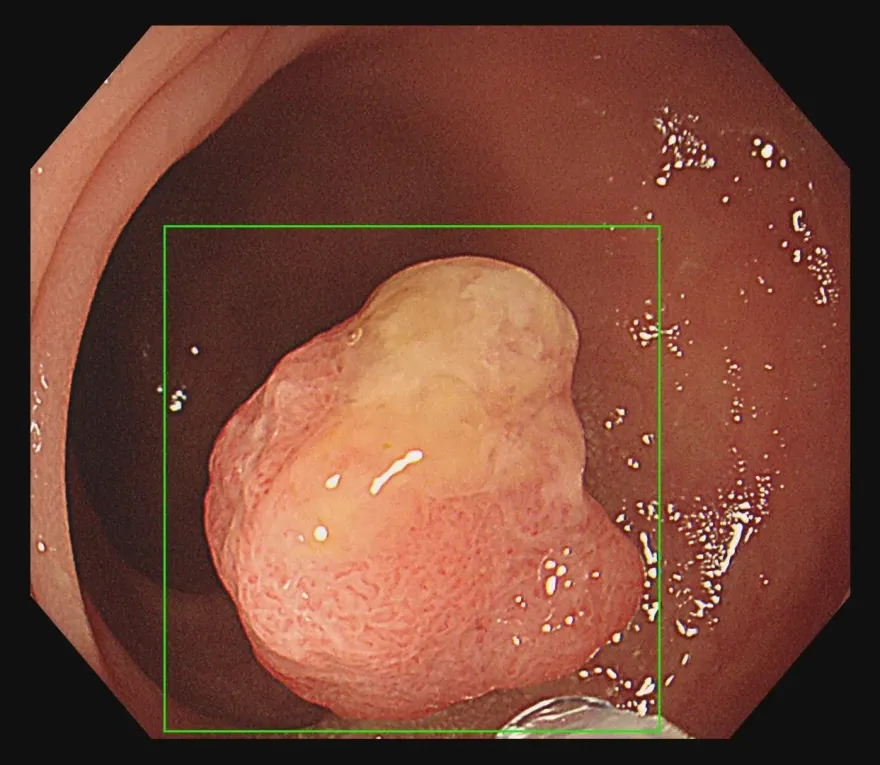

大腸癌

糞便潛血

腫瘤

切除

瘜肉

大腸鏡

息肉

糞便

血便